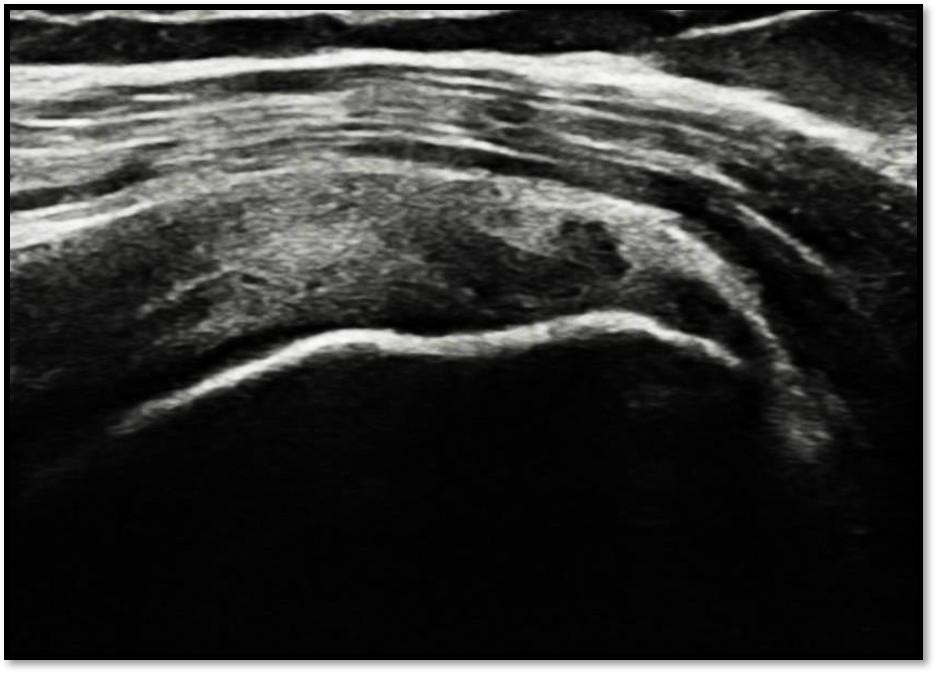

케이스 1: 관절면측 파열 → 축소봉합술

환자: 45세 남성, 테니스 동호회

진단:

MRI: 극상건 관절면측 부분파열 (약 40%)

파열 양상: 가로 파열, 깔끔함

치료:

축소봉합술 (특수 드릴 + 콜라겐 봉합사)

재생주사 병행

재활 운동

결과:

12주 후 초음파: 봉합 부위 안정적 유지

6개월 후 테니스 복귀